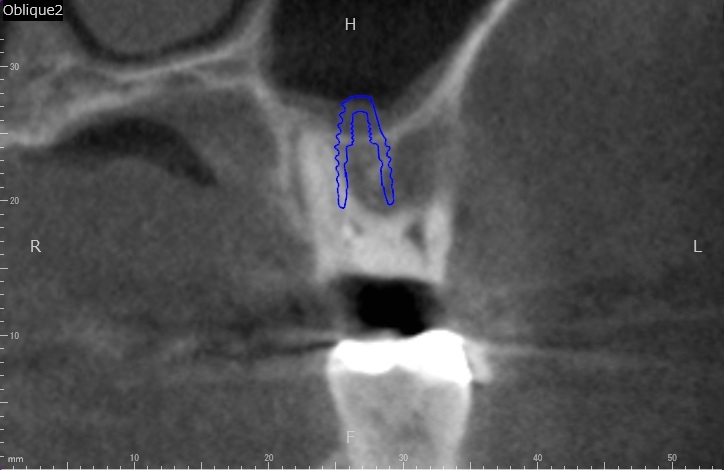

歯科用CTによる精密な検査

当院では必ず精密検査として、歯科用CTによる撮影を行います。顎の骨の状態、血管・神経の位置を正確に把握することで、手術の安全性が高まります。

CT画像は、インプラントの埋入のシミュレーションにも使用します。

2検査・診断

虫歯や歯周病の検査、レントゲン検査、CT検査などを行います。CT検査は、顎の骨の状態、血管・神経の位置を正確に把握し、シミュレーションをするために不可欠な検査となります。